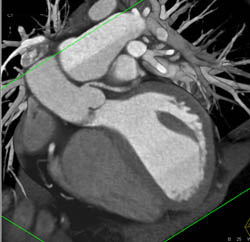

LAD Disease